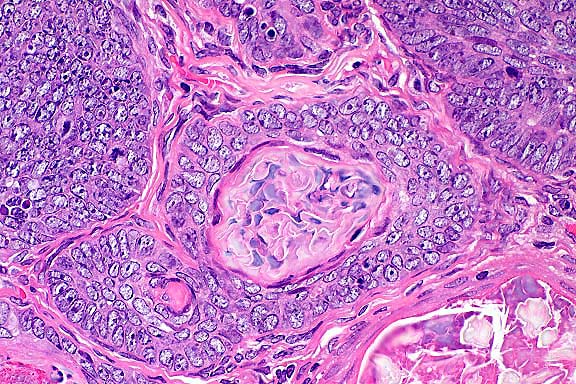

Исследование: микропрепарат молочной железы в медицине

Раздел: Снимки-откровения